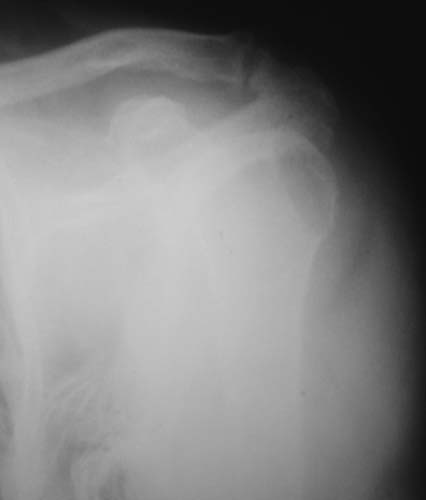

r1r2r3

Уважаемые коллеги!Женщина, 60 лет. 3 недели назад упала с упором на отведенную левую руку. Почувствовала боль в левом плечевом суставе. За помощью не обращалась. 2 недели "мази и припарки". Затем - рентгенограмма (r1 и r2), жалобы на боли,ограничение движений...

Активное отведение 80 гр., при пальпации - головка плечевой кости безболезненно вправляется и тут же самостоятельно вывихивается. Наложена косыночная иммобилизация, рентгенография (r3) и МРТ.В нашем диагностическом центре МРТ исследование плечевого сустава выполнено впервые, опыта у нас маловато :(.Вопросы: уточнение диагноза? какие исследования провести? тактика лечения?

"Прицельная" съемка малопонятного очага.

1. На рентгене - нижний подвывих плеча и очаг остеолиза суставного бугорка с четкими контурами (вдавленный перелом на фоне остеопороза ? доброкачественная опухоль? аваскулярный некроз ? (хотя ни разу не слышал об аваскулярном некрозе плеча..)

Судя по снимкам, речь идTт о типичном случае Hill-Sachs Lesion. По этому поводу я позволю себе некоторый экскурс:

97 % всех вывихов плеча происходит по механизму комбинации отведения, разгибания и наружной ротации (А. Гринспан). В момент вывиха головка плеча ударяет о нижний край гленоида, что ведет к вдавленному или компрессионному перелому одной или обеих структур. Чаще всего, однако, повреждение возникает в задней латеральной области головки плечевой кости на переходе от головки к шейке. Этот диагноз можно выставить на основании рентгеновского снимка в переднезадней проекции с внутренней ротацией плеча. Несколько реже видно повреждение гленоида о передненижний перелом края. То, что мы называем Bankart Lesion. Это повреждение видно на ре. снимке в п.з. проекции при нейтральной позиции плеча. Разумеется хрящевые и мягкотканные повреждения (в смысле Банкарт) мы увидим лучше всего на ЯМР.